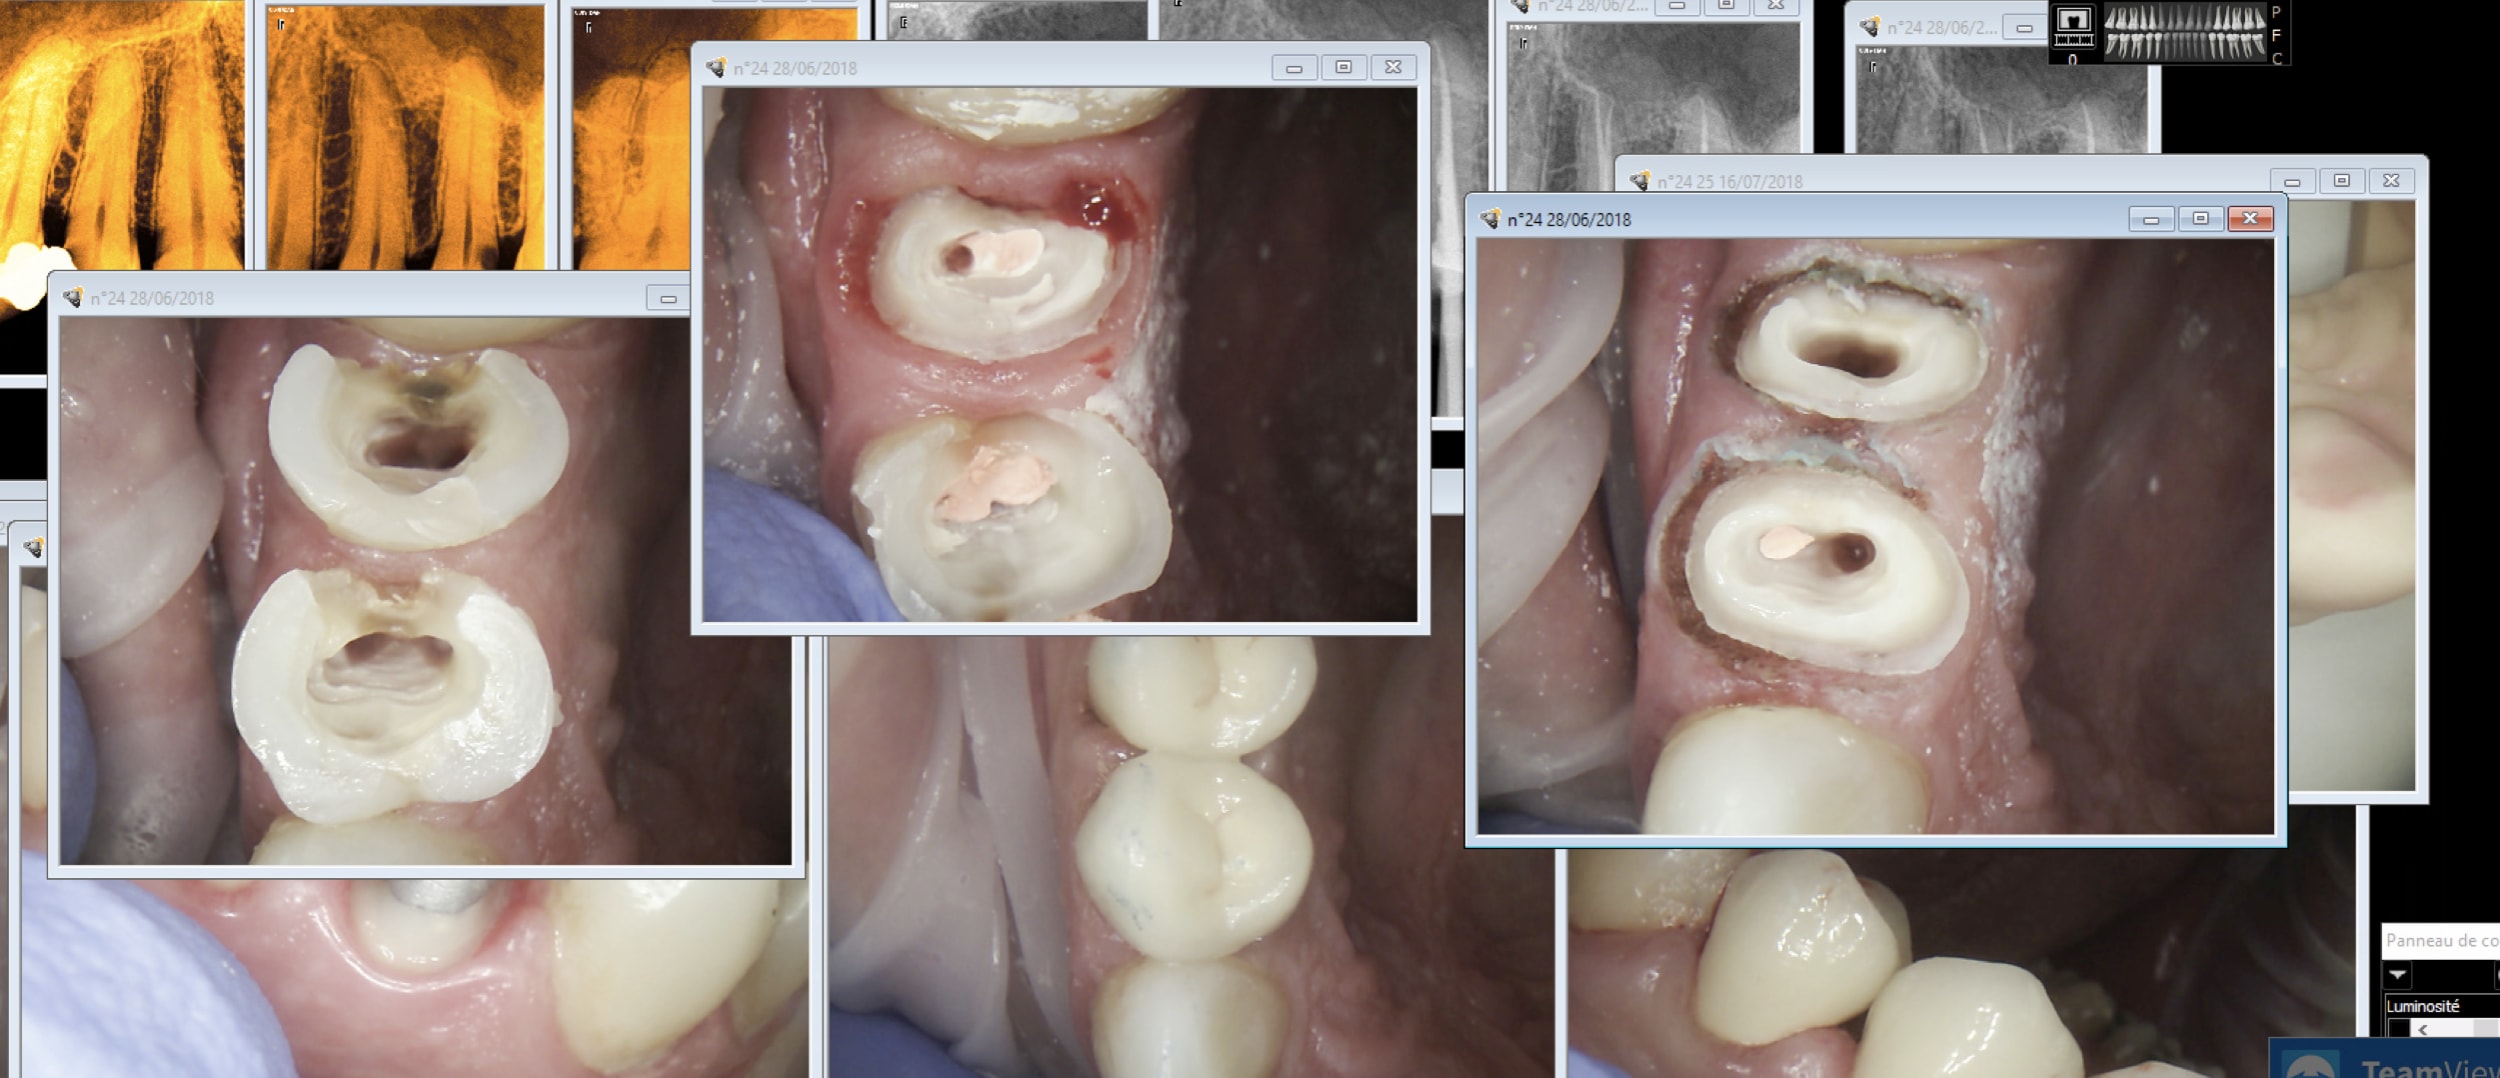

Encore 2 zigouigouis.

Capture d écran 2018 07 16 16.46 - Eugenol

Bon sur ce coup j'ai joué du laser.